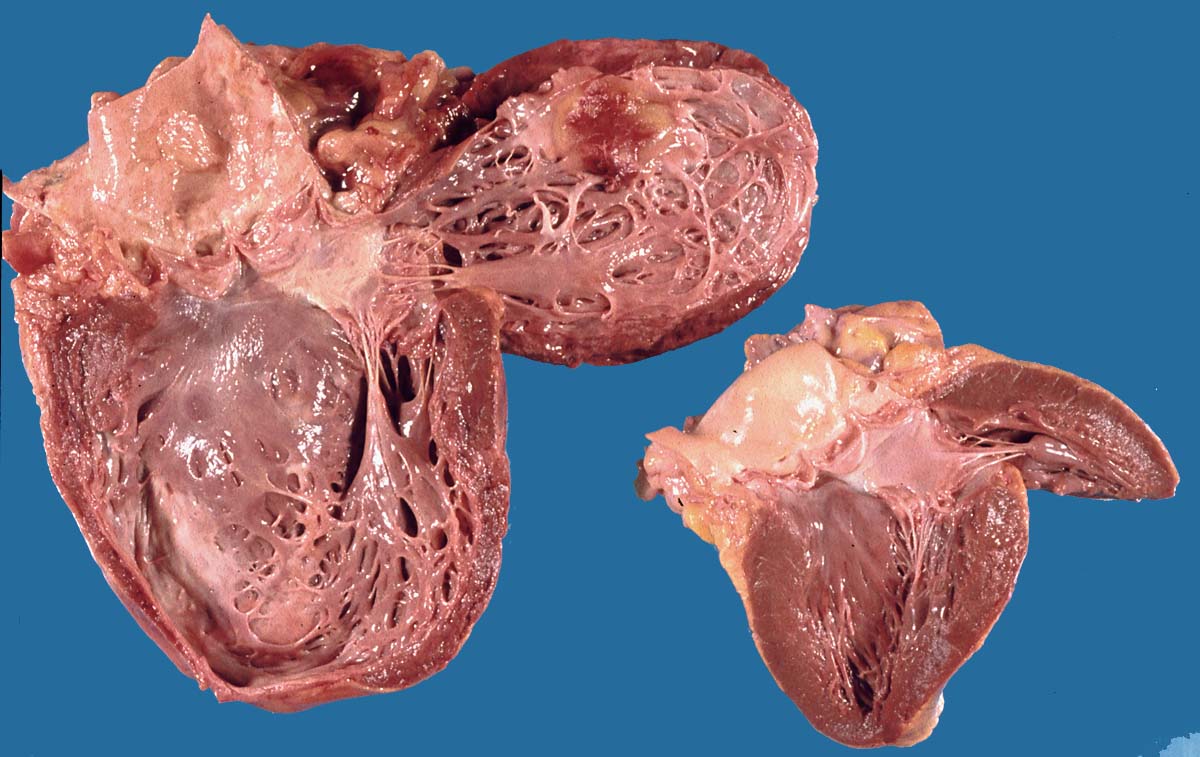

PathoPic – image database / PathoPic ID 8658 - Herzwandaneurysma

Herzwandaneurysma

vaskulär / Durchblutungsstörung

Herz

Kardiovaskuläres System

Makroskopie